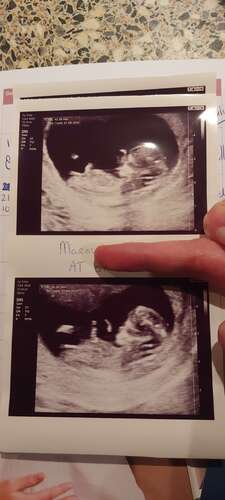

Hier nog eentje.. 13+5

13.3 hier. Is hier een nub te zien? 💗💙

13+4 weken.. Kan iemand iets zien? Ik vind het zelf erg lastig om te bepalen waar de nub zit